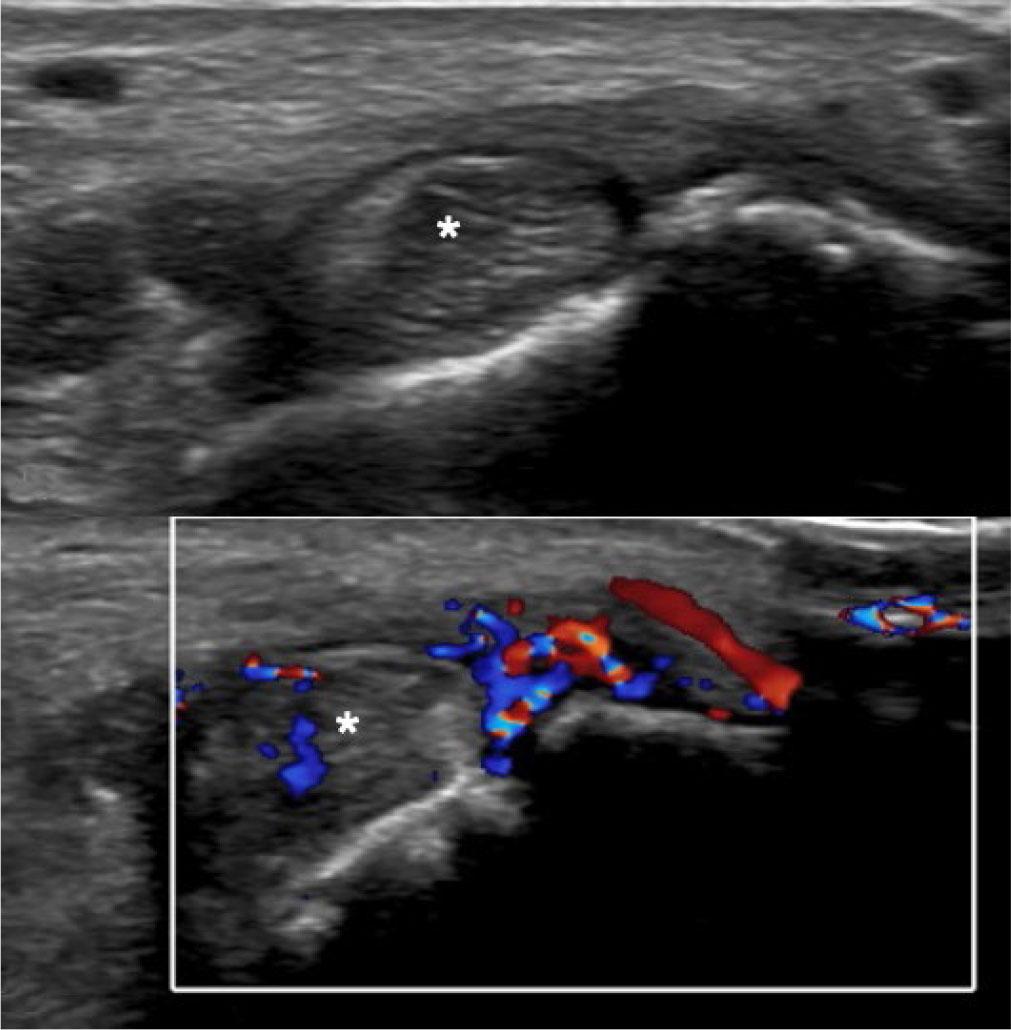

Synovial hypertrophy (SH) in US is defined as abnormal hypoechoic (relative to subdermal fat, but sometimes isoechoic or hyperechoic) intraarticular tissue that is non-displaceable and poorly compressible(4) (Fig. 2). These features help in differentiating synovial hypertrophy from joint effusion (Fig. 3).

Synovitis. Long-axis US image of the suprapatellar knee showing echogenic synovium (asterisk in A) which is partially compressible on probe pressure, as seen in image B. Arrows indicate the quadriceps tendon

Synovitis is diagnosed when synovial hypertrophy exhibits signal on color flow Doppler interrogation (Fig. 4). PD is considered more sensitive than CD in identifying and quantifying increased vascularity and can be used to monitor disease activity and treatment response(5). Szkudlarek et al.(6) developed a semiquantitative grading of the PD evaluation of synovitis: grade 0 – no flow; grade 1 – single-vessel signals; grade 2 – less than half of the area of the synovium-filled with vessels; grade 3 – more than half of the area of the synovium filled with vessels (Fig. 5).